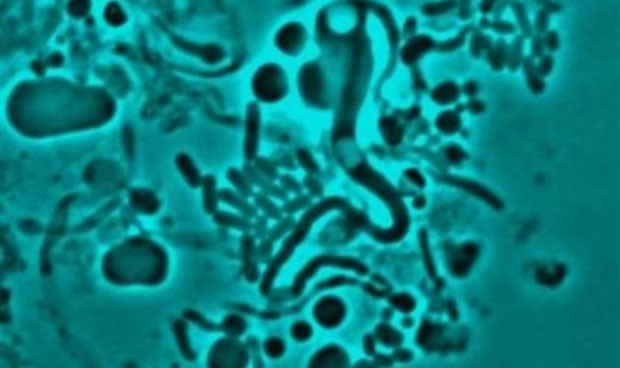

Científicos de la Universidad de Newcastle (Reino Unido) han confirmado por primera vez que las bacterias pueden cambiar de forma para evitar ser detectadas por los antibióticos en el cuerpo humano.

Estudiando muestras de pacientes ancianos con infecciones recurrentes del tracto urinario, este equipo de investigación utilizó técnicas de última generación para identificar que una bacteria puede perder voluntariamente su pared celular, el objetivo común de muchos grupos de antibióticos.

En esta forma en L, las bacterias son débiles y más débiles, pero algunas sobreviven, escondiéndose dentro del cuerpo. Esta investigación también ha captado por primera vez en vídeo este movimiento, en una bacteria en forma de L aislada de un paciente con una infección del tracto urinario que reformó su pared celular después de que el antibiótico desapareciera, lo que ocurrió en apenas 5 horas.